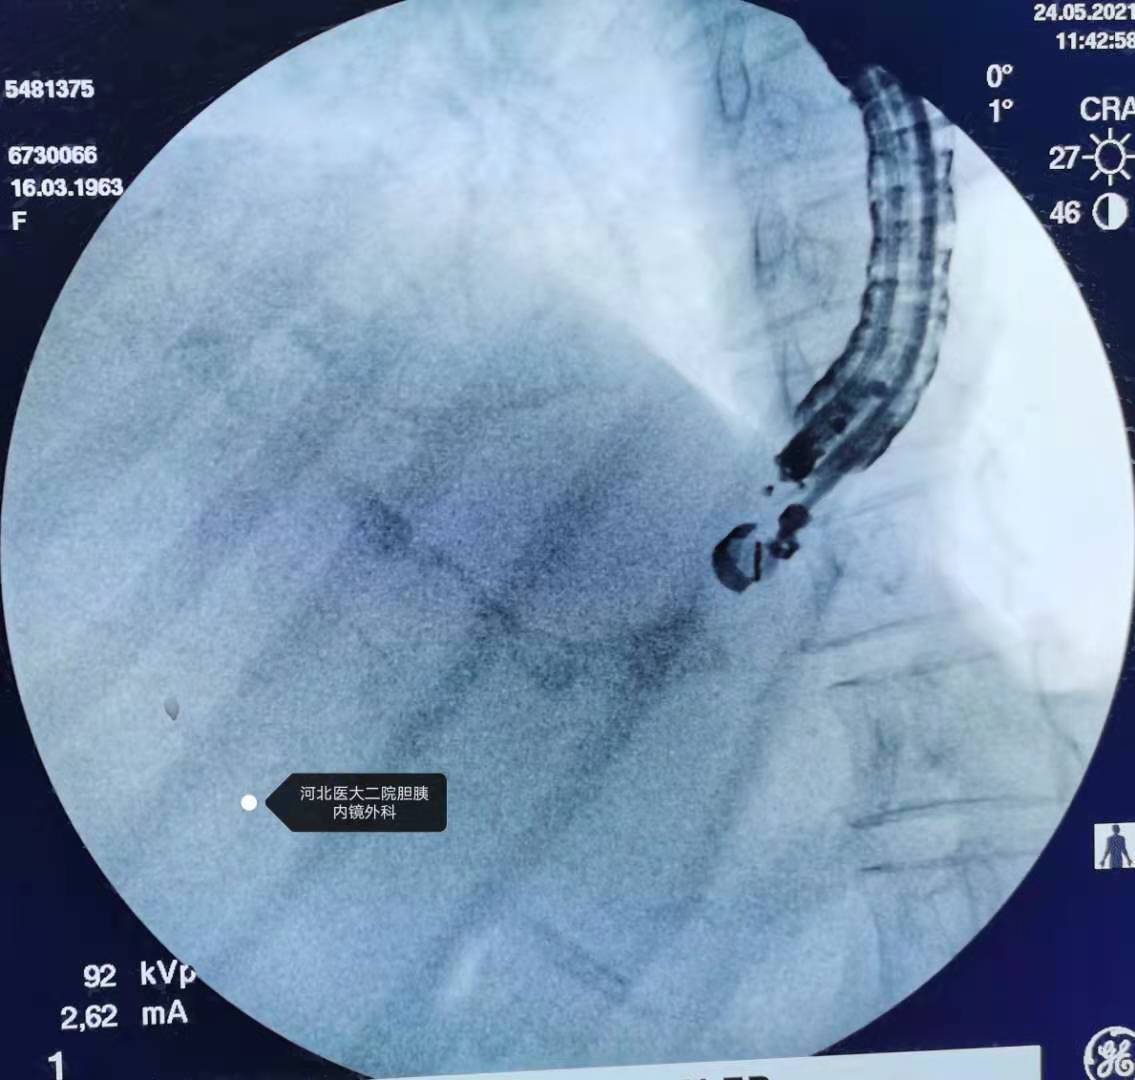

造影。

其实开始导丝转了180°,到了下面箭头所示位置,调整后还是进去了上游胆管方向。